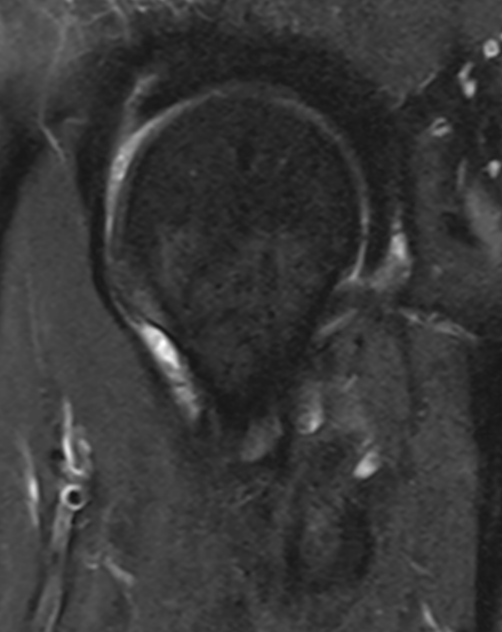

Sagittal cam lesion of femoral head-neck junction